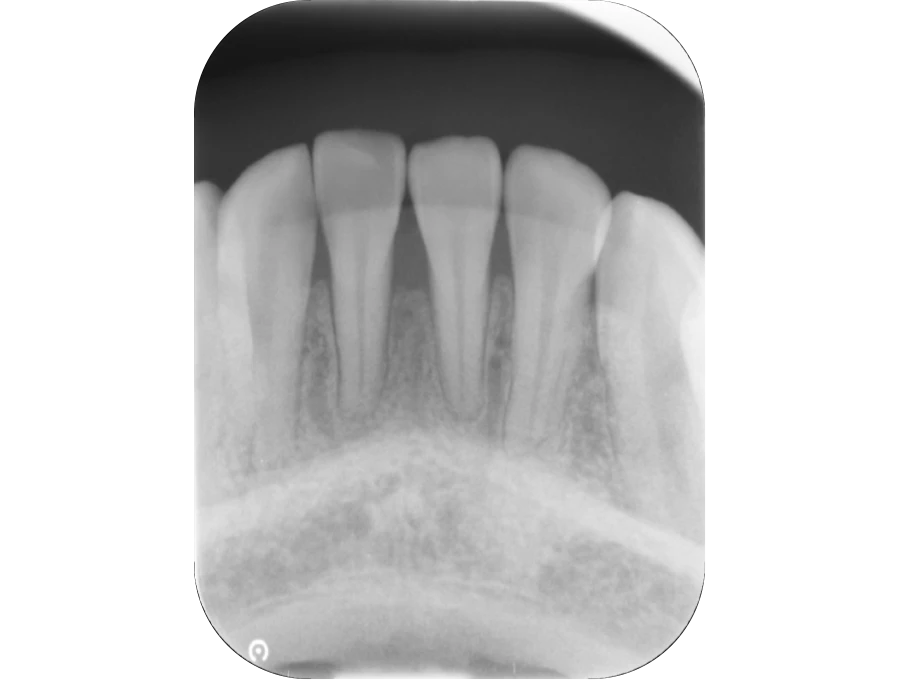

正確な診断

歯周ポケット測定やレントゲン・CT解析など、多角的な検査で歯周病の進行度と原因を正確に把握します。患者さま一人ひとりに最適な治療計画を立て、根拠ある治療につなげます。

精密検査

実際にお口の中の状態をチェックしていきます。レントゲン撮影にて歯や骨の検査を行い、虫歯や治療痕のチェック、歯周病検査などの各種検査を行い、総合的な診断を下します。